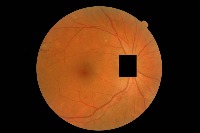

hard-exudate-detection1 Computer Vision Project

Diabetes Retinopathy Diagnosis: Medical professionals could use hard-exudate-detection1 to identify diabetic retinopathy in patients during routine screenings or for diagnosing symptoms, as hard exudates are a typical sign of this medical condition.

Automated Retinal Image Analysis: The identification of hard exudates could provide crucial information for automatic retinal image analysis software. It would provide an extra tool for detailed assessment of retinal images, providing comprehensive and accurate results.